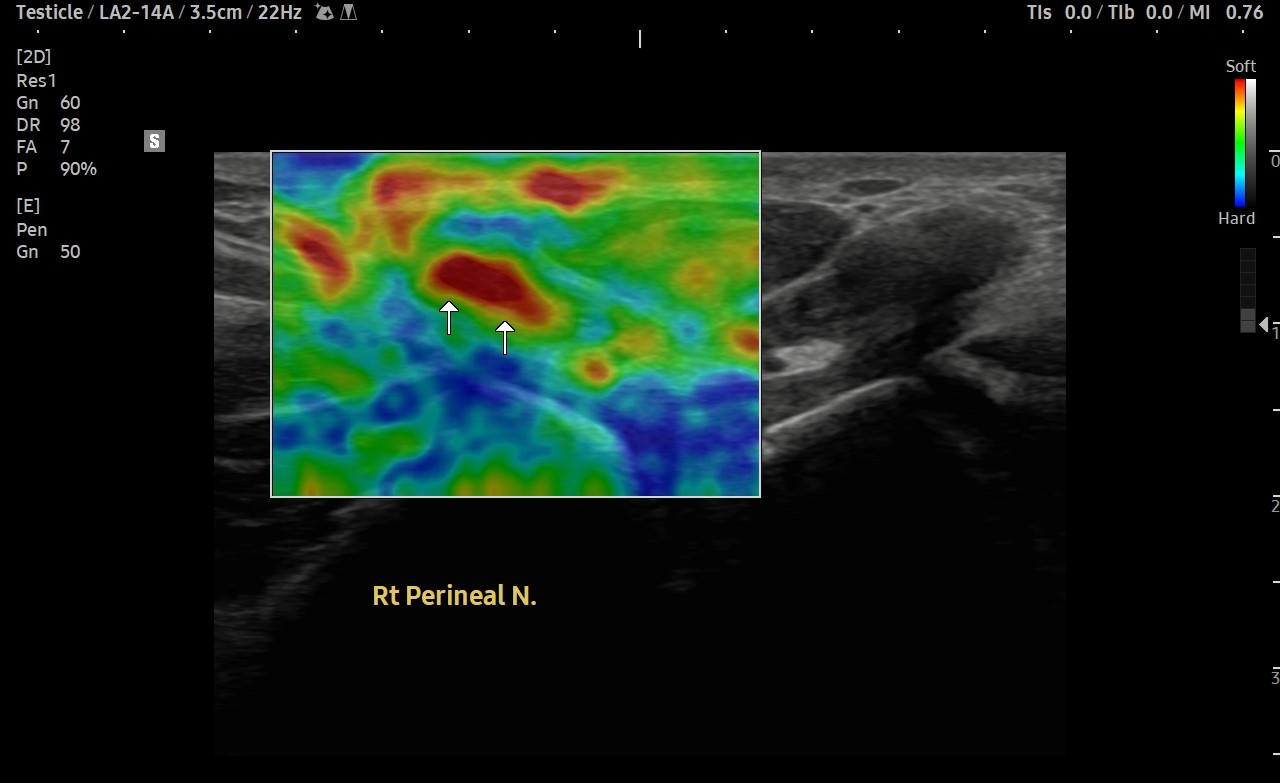

[치료 전]

[치료 후]

- 치료횟수 : 40 회